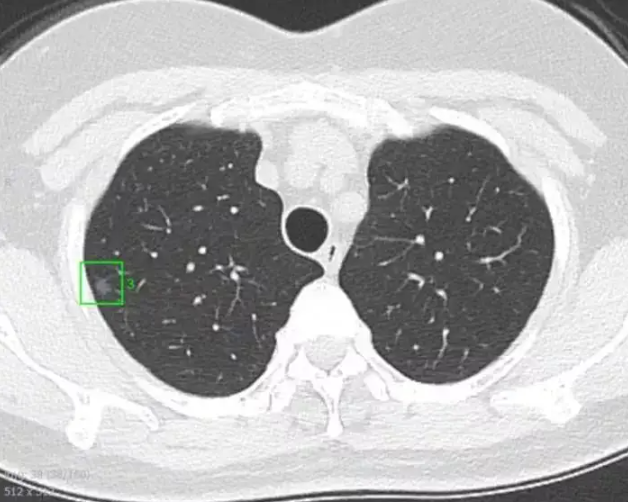

放射科医生阅读CT片时,会将直径小于3厘米的小病灶称为肺结节,这些病灶在肺部视野中清晰可见,被肺实质包裹;直径大于3cm的称为肿块。肺结节患者通常无症状,且不伴有肺门淋巴结肿大、肺不张或胸腔积液等其他影像学改变。

肺结节可以是单发或多发。在发现肺结节后,重点是评估结节是恶性还是良性。恶性肺结节的常见病因包括原发性肺癌、类癌肿瘤和肺转移癌;良性肺结节的常见病因包括感染性肉芽肿(最常见的是真菌感染,如组织胞浆菌和球孢子菌感染,以及结核分枝杆菌感染)和良性肿瘤,如错构瘤。也有一些不常见的原因,如肺血管病变和炎症性病变。常见病因包括遗传性出血性毛细血管扩张、肉芽肿性多血管炎、类风湿性关节炎、结节病等。